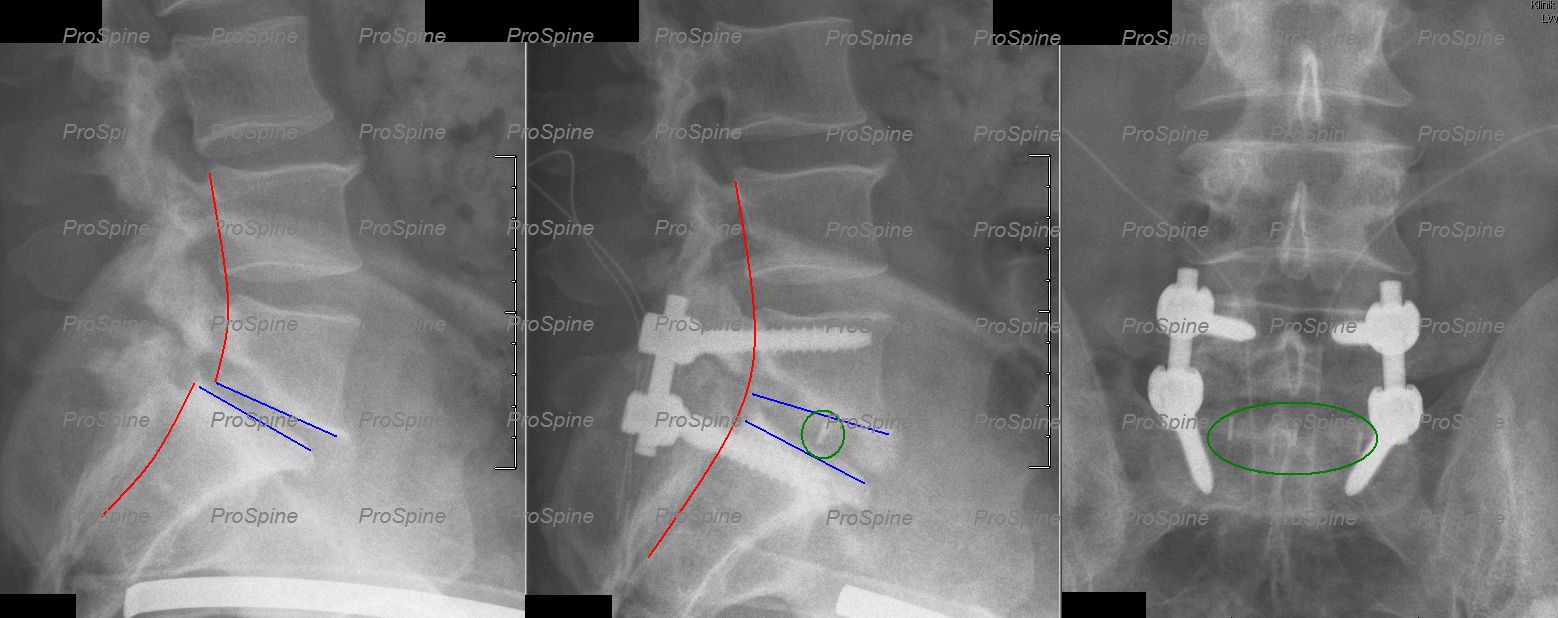

Větším výkonem je dekomprese - odstranění zúžení (Obr. 8) kombinovaná většinou se stabilizací páteře. Ke stabilizaci bederní páteře se ponejvíce používají systémy složené ze šroubů a tyčí, implantované ze zadního operačního přístupu, jimiž lze stabilizovat libovolný počet segmentů. Z tohoto přístupu je možné i provést výměnu meziobratlové ploténky za fúzní implantát. Metoda se nazývá PLIF (posterior lumbar interbody fusion- zadní bederní fúze mezi těly obratlů), kdy je operační přístup veden přímo přes páteřní kanál, nebo TLIF (transforaminal lumbar interbody fusion- transforaminální bederní fúze mezi těly obratlů), kdy je operační přístup veden přes foramen, kudy opouští páteřní kanál nervové kořeny. Ploténka je u metod PLIF a TLIF nahrazena implantátem- meziobratlovou klecí (v v dnešní době nejčastěji z titanu, nebo PEEKu- polyeter-eterketonu) v kombinaci s kostními štěpy (Obr. 9). Stejné implantáty jsou užívány i v  případě meziobratlové stabilizace z předního operačního přístupu- přes břicho (ALIF - anterior lumbar interbody fusion- přední bederní fúze mezi těly obratlů). V případě segmentů L2-3-4 lze jako alternativu k ALIF použít metodu XLIF (eXtralateral lumbar interbody fusion, obr. 10), která je prováděna z boku a jejíž výhodou je nižší invazivita, neboť v přístupu k páteři nestojí oproti metodě ALIF v cestě velké cévy- aorta a dolní dutá žíla. V případě spondylolistézy je možné zadní stabilizaci kombinovat se všemi výše zmíněnými metodami mezitělové fúze, vhodné je provést repozici.